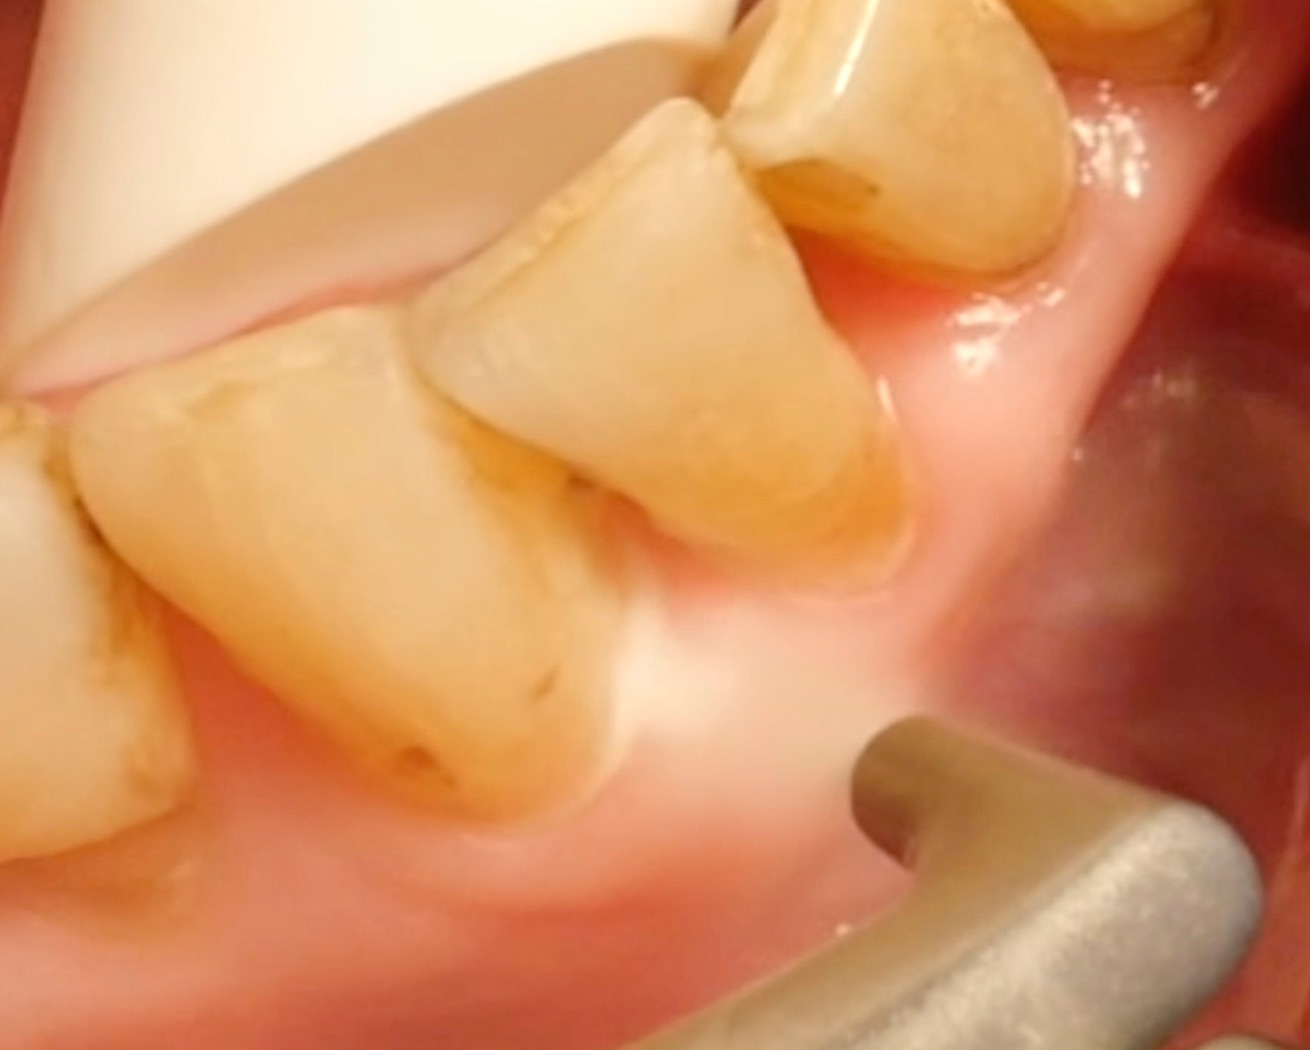

Air polishing devices have become a firmly established part of periodontal treatment in recent years. But how efficient are they? What applications do they have? What should be considered when using them?

• For pocket probing depths of ≤ 4 mm and of 5–9 mm, removing biofilm with an air polisher is more effective and quicker than conventional methods; however, the clinical outcome is comparable, and no method is clearly superior.

• However, it is essential to note that air-polishing devices cannot ablate deposits of tartar and calculus; here, a combination of (ultra)sonic devices and/or hand instruments must be used.